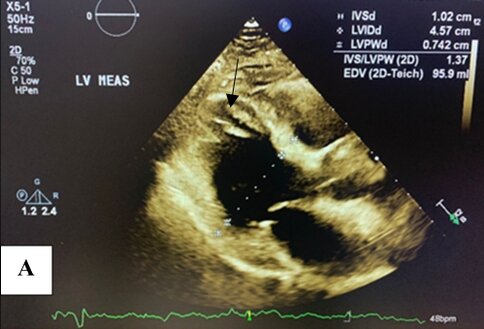

Left ventriculography demonstrated a normal-sized left ventricle with apical akinesis and basal hyperkinesis, resulting in the characteristic "apical ballooning" pattern seen in Takotsubo syndrome (TTS). An apical thrombus was also identified (Figure 4(a) and (b)).

Figure 4. Left ventriculography demonstrating apical akinesis and basal hyperkinesis, consistent with Takotsubo cardiomyopathy. An apical thrombus is clearly identified at the left ventricular apex (black arrow) in both diastole and systole views. (A) End-diastolic frame; (B) end-systolic frame.